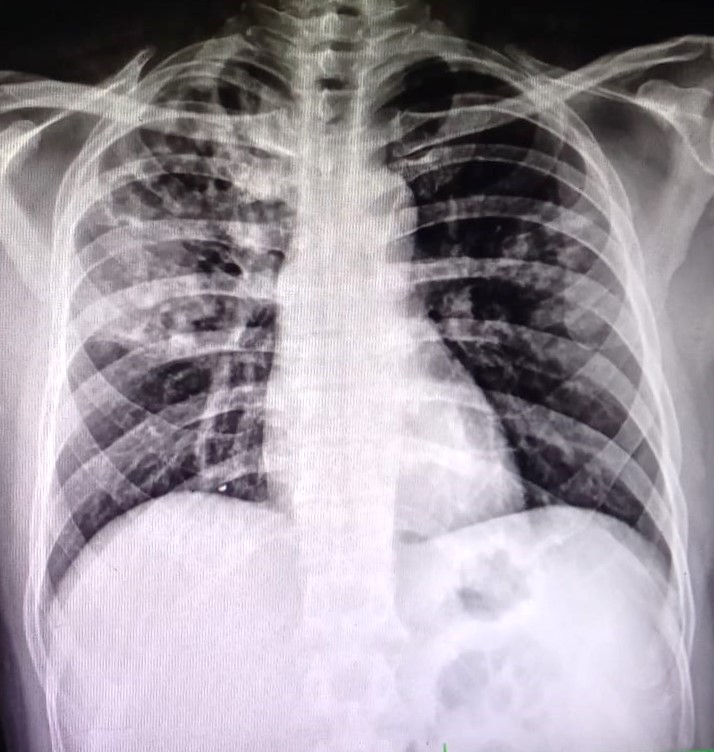

| 1 | IGGMC, Nagpur, Nagpur | P2 | 29-4471 Follow-up of 29-4404 |

Gaurav Wankhede | Consent taken on Paper | 19 Yrs. |

Provisional Diag : Pulmonary Tuberculosis

Final Diag : Disseminated TB ( Abdomen TB), Pulmonary Tuberculosis |

TB Case (Confirmed) | Left Sided Pleural Effusion | Abnormality visible on x-ray |